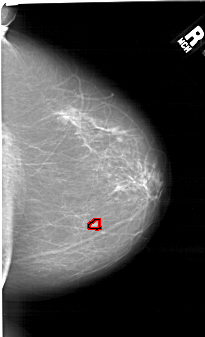

A_1499_1.RIGHT_CC

RIGHT_CC LINES 6391 PIXELS_PER_LINE 3886 BITS_PER_PIXEL 12 RESOLUTION 43.5 OVERLAY

FILE: A_1499_1.RIGHT_CC.OVERLAY

TOTAL_ABNORMALITIES 1

ABNORMALITY 1

LESION_TYPE MASS SHAPE LOBULATED MARGINS ILL_DEFINED

ASSESSMENT 4

SUBTLETY 3

PATHOLOGY MALIGNANT

TOTAL_OUTLINES 1

BOUNDARY